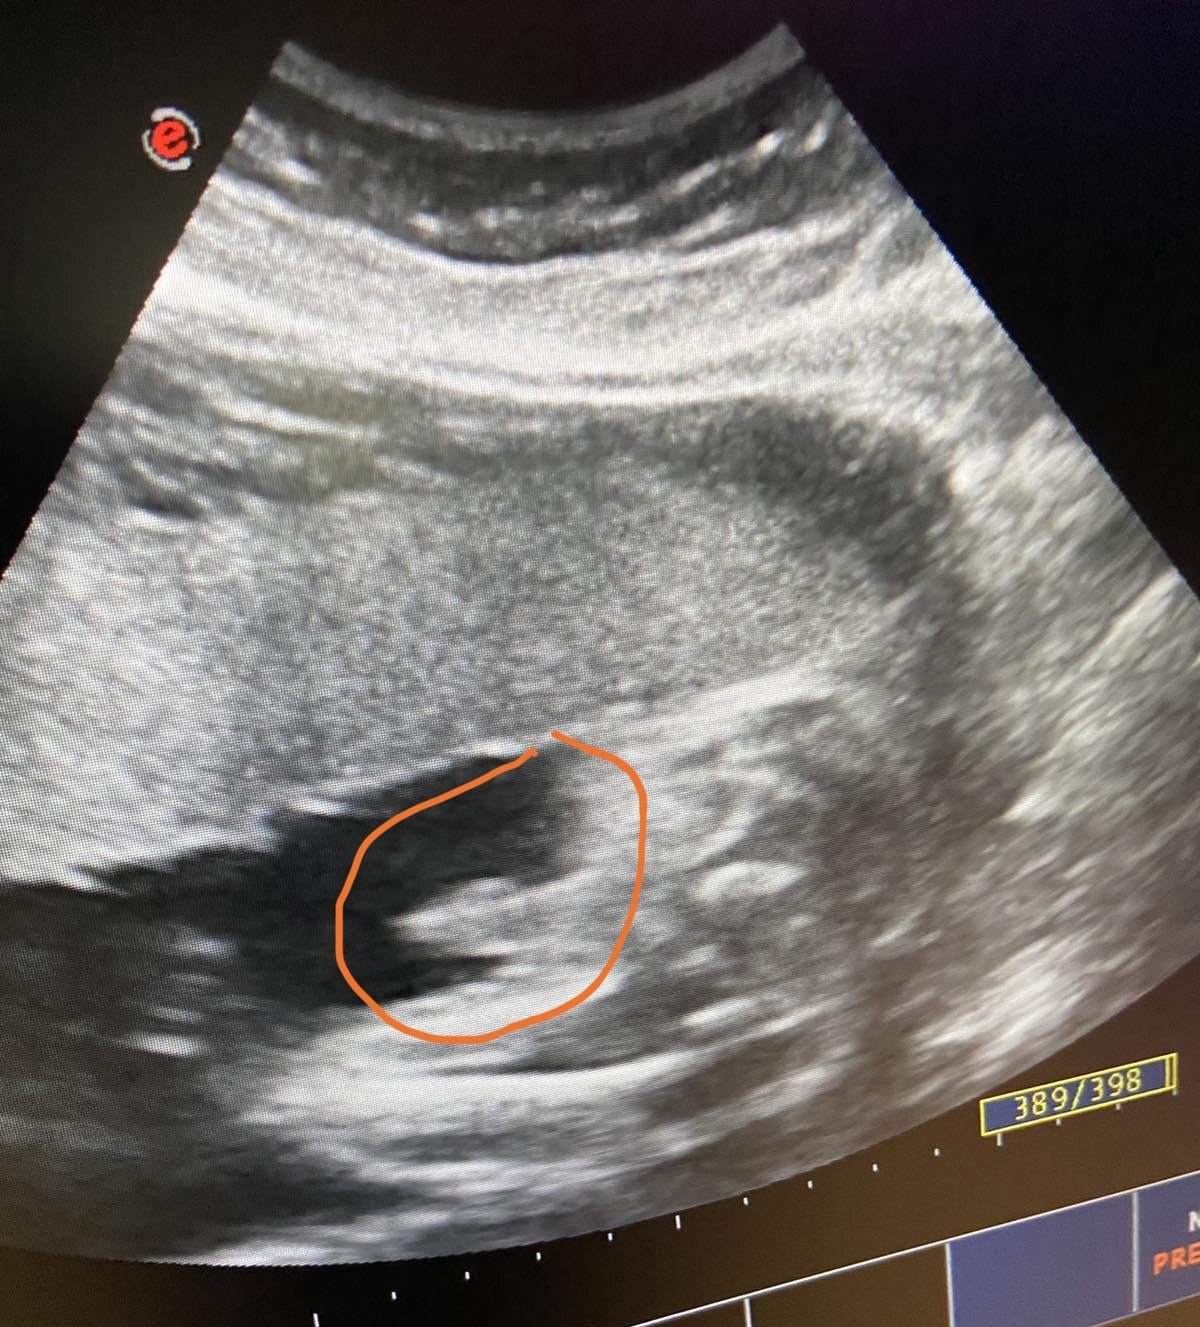

Здравейте прекрасни мами🌸 ние имаме малък “проблем” 😁 не можем да разберем какъв е пола на бебето а юли месец чакаме  прекрасната рожба 🥰 на тази снимка съм оградила нещо в което се колебаят дали е момче но не са сигурни🤔 и сега мама и тати са в пълно невидение

GrinningАз не разбирам много, но на мен това ми прилича на ръчичка. Пък и като не знаеш, вълнението е по-голямо,нали. И аз в четвъртък бях на преглед, 31 гс, бебето е 2 кг.

На мен също ми прилича на ръчичка 😁 нооо.... за специалистите май не е 🤔 вълнувам се страшно много и го чакаме с нетърпение 🥳 аз си приготвих две шишенца и една залъгалка🍼 предпочитам да имам в себе си отколкото да се разправям със сестрите.А за помпата разбрах че е за предпочитане на 101% 👍